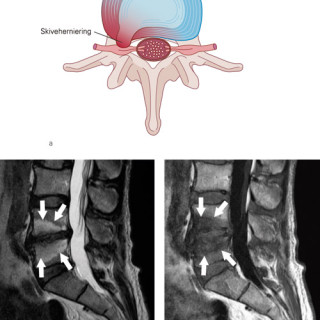

Artrose er sykdom i et synovialt ledd. Det synoviale leddet er et organ bestående av leddbrusk, subkondralt bein og en leddkapsel, som på innsiden er kledd med synovialmembran og på utsiden er forsterket av ligamenter. Sykdommer som primært rammer én av komponentene i et ledd, vil etter hvert medføre sekundære forandringer i de øvrige (fig 1), og det utvikles en leddsvikt som gir pasienten smerter og nedsatt funksjon. Alle ledd kan rammes, men artrose er vanligst i hånd, hofte og kne. Det følgende er en oversikt over epidemiologiske og patologiske forhold, årsaksmekanismer, utredning og...